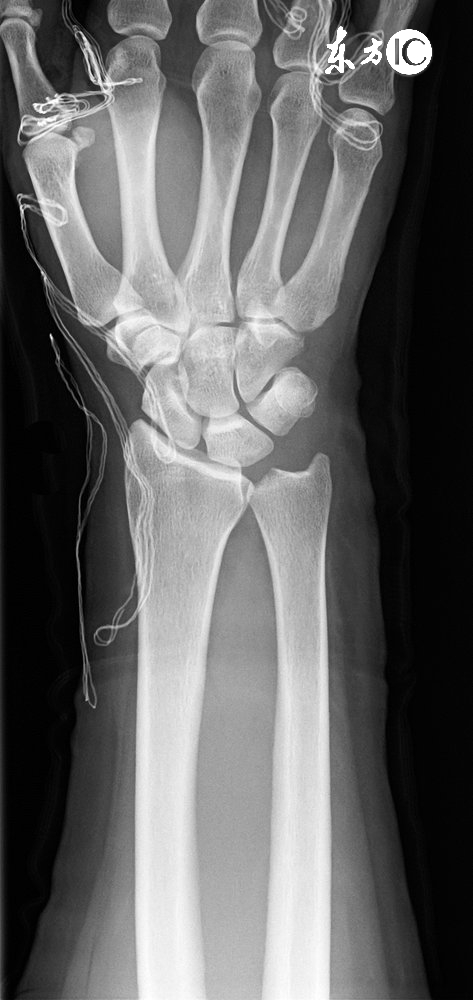

我有一个患者,六月中旬经人介绍找到了我。当时她右腿膝盖疼痛,尤其在上下楼的时候,要单腿错步才敢一节节的下楼梯,走平路时时间稍微长点(200米左右)就感觉到膝盖发软,无力支撑,需要休息一会儿才能继续行气。到医院拍片,影像显示在膝关节外侧下方有一游离体,故诊断上述症状是游离所致,啊、属于骨质增生,建议让手术取出此物,消除不适症状。

我用拇指按压她膝盖周边部位,发生右膝外侧上面部分有一明显压痛点,其他部位没有发现具体压痛点,但该压痛点与影视提示的游离体位置并不相同。我给她开了一个药酒方,灵仙50克,乳香没药各15克,川草乌各3克,麝香1克,回去后用白酒浸泡7日,7日后外涂病灶部位,也就是压痛点的地方,以缓解该部位的疼痛症状。同时嘱咐她让膝盖处于一种舒服的位置,不要过于劳损,平时注意保暖,不要受寒。